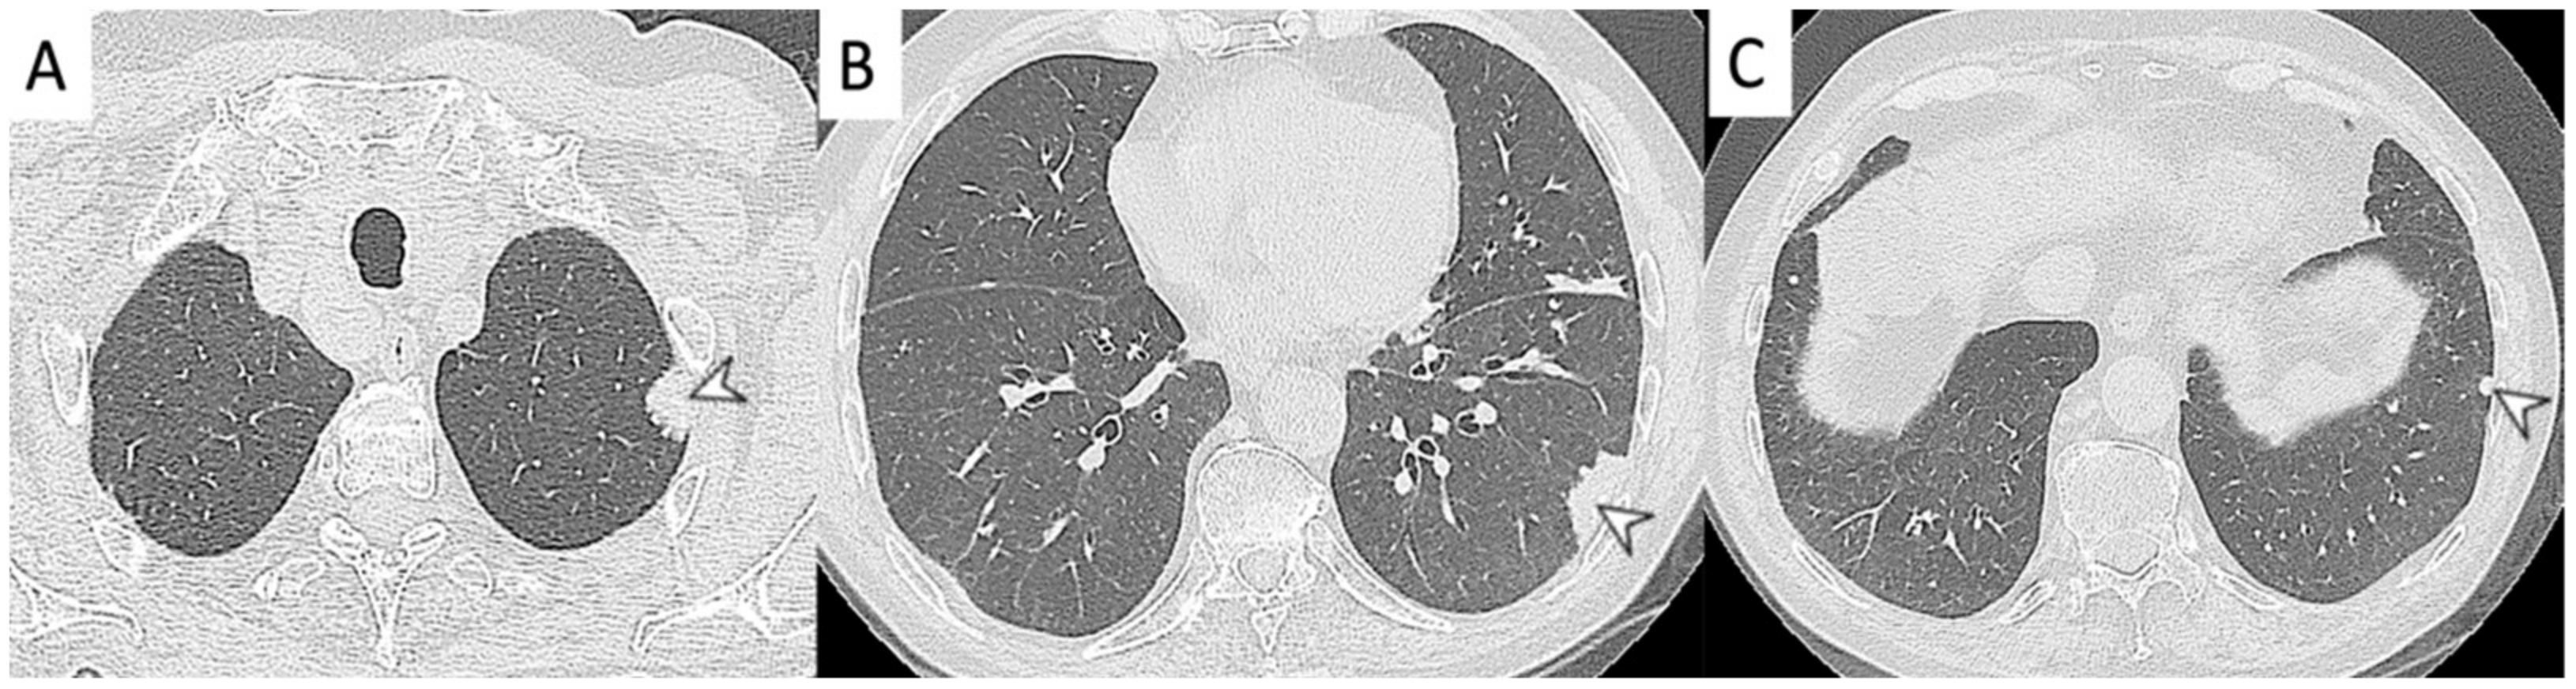

2.5. Eosinophilic Granulomatosis with Polyangiitis (EGPA-Churg-Strauss)

| EGPA | Migrant GGOs, transient consolidation, irregular bronchial wall thickening, small nodules with peribronchial and centrilobular distribution, pleural effusion. |